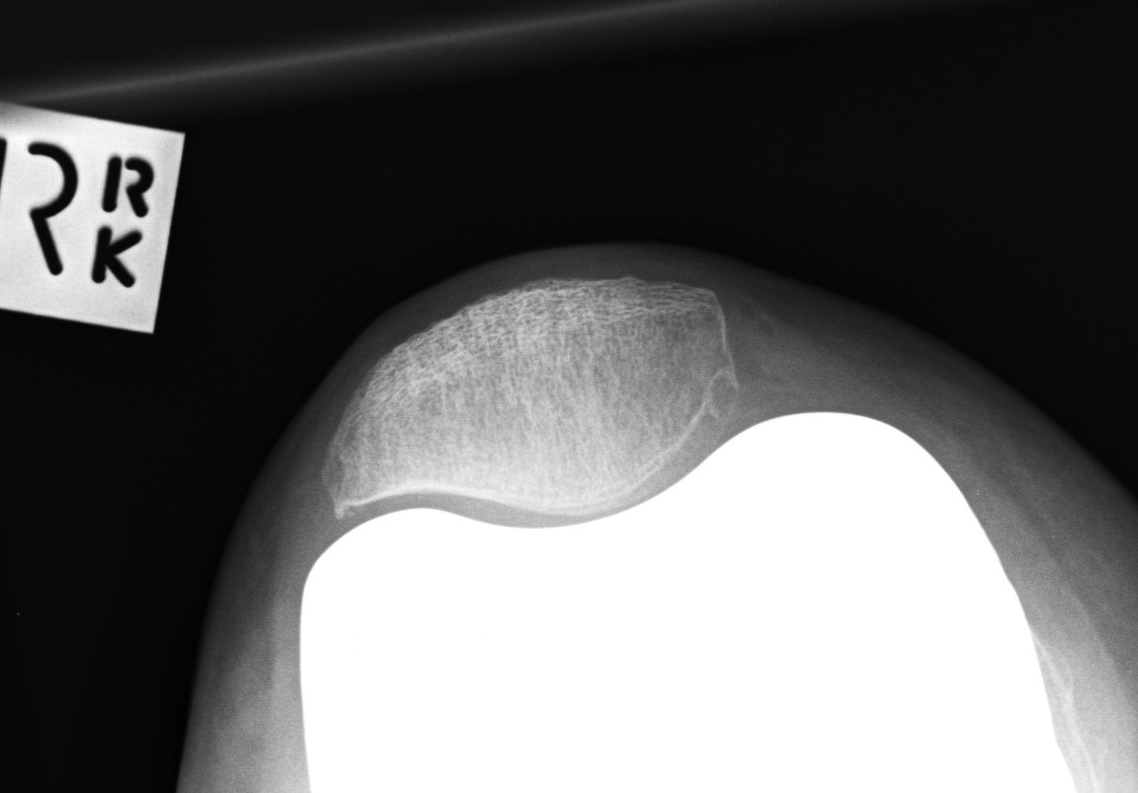

Xray

- skyline views

- lateral tilt / subluxation